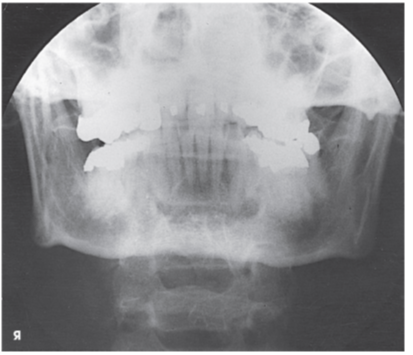

What projection and anatomy is demonstrated in the image below?

AP axial of the TMJs

PA axial of the mandibular rami

PA of the mandibular body

Axiolateral oblique of the mandibular body